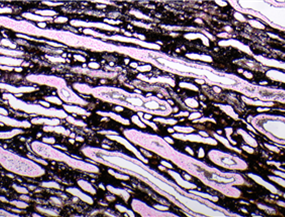

BMT Scheme

Here’s a slide from the BMT scheme. Marks were deducted for background staining and non specific silver deposit which are masking the demonstration of the fibres. This slide scored 5/10.